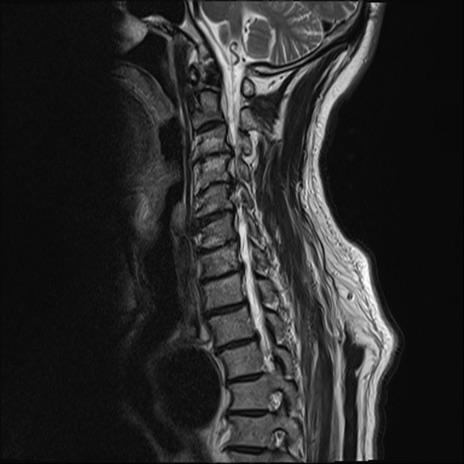

【整形】TIPS症例7 頚椎MRI T2WI(矢状断像)

頚椎MRI

矢状断像と横断像